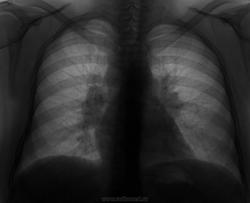

Женщина, 38 лет, пришла для плановой флюорографии, при расспросе выясняется, что уже давно кашляет,в анализе крови в декабре СОЭ 37 мм/ч, причину повышения цифр списали на гинекологию, больше не обследовалась.Снимок 2010г прилагаю

Саркоидоз ВГЛУ?

Аденопатия корней - на КТ

Лимфома, mts, tbs, опытные коллеги поправьте, если что )

при поражении паратрахеальных, трахеобронхиальных и бифуркационных лимфатических узлов лучше всего сделать медиастиноскопию с биопсией;  если это возможно, где Вы проживаете. Я встречал подобную картину при лимфоме Ходжкина, хроническом лимфолейкозе. Считаю, что коллегам будет интересен конечный результат. Ждем сообщений. С уважением Nik.

Дополнение к #5. Первая версия - саркоидоз органов дыхания I. Медиастиноскопия. Диагноз подтвержден морфологически.Обнаружены клетки Березовского-Штернберга-Рид. С уважением Nicolas

Если есть увеличенные периферические лимфатические узлы, склонился бы к ЛГМ.

только довольно-плотный увеличенный л/у по передне-латеральной поверхности шеи.

По снимку увеличены  и паратрахеальные л/узлы, по моему больше данных за ЛГМ. Ну, а если есть периферия все проще необходима биопсия.